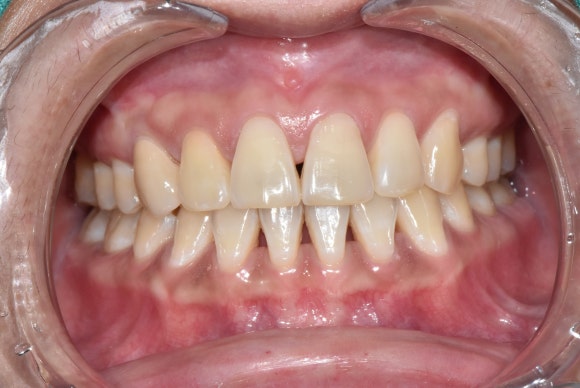

치수괴사로 인한 변색, 어떻게 치료하나요?

치수의 괴사가 원인이기 때문에,

변색의 원인도 치아의 내부에 있습니다.

먼저 신경치료를 통해 괴사된 치수조직들을 모두 제거합니다.

제거된 후 비어있는 공간은 신경치료 약제로 꼼꼼하게 밀봉합니다.

그 위로 미백제를 넣고 임시충전재로 가봉을 하지요.

미백제를 1주일 간격으로 2~3번 정도 교체하고나면 대개 하얀 치아로 돌아오게 됩니다.

(선천적인 치아 색상의 불균형이나 무늬는 사라지지 않으니, 치료 전 치과보존과 전문의인 서울재생치과 준원장과의 상담을 권합니다.)

치아가 변색되었다고 해서

반드시 라미네이트나 크라운 같은 보철치료를 선택해야 하는 것은 아닙니다.

서울재생치과 준원장은 원인해결과 과학적인 근거에 기반을 둔 합리적인 치료를 지향합니다.